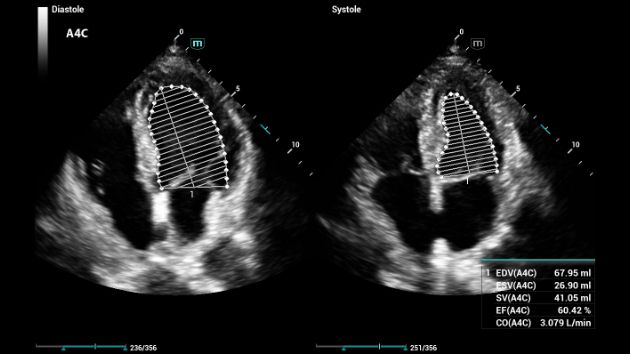

Consona presenta soluzioni nuove e concrete, che aiutano a effettuare diagnosi efficaci con semplicitĂ , rivolgendosi a un'ampia platea di pazienti. La serie mette a disposizione strumenti estremamente avanzati per rimanere all'avanguardia nella diagnosi cardiovascolare.